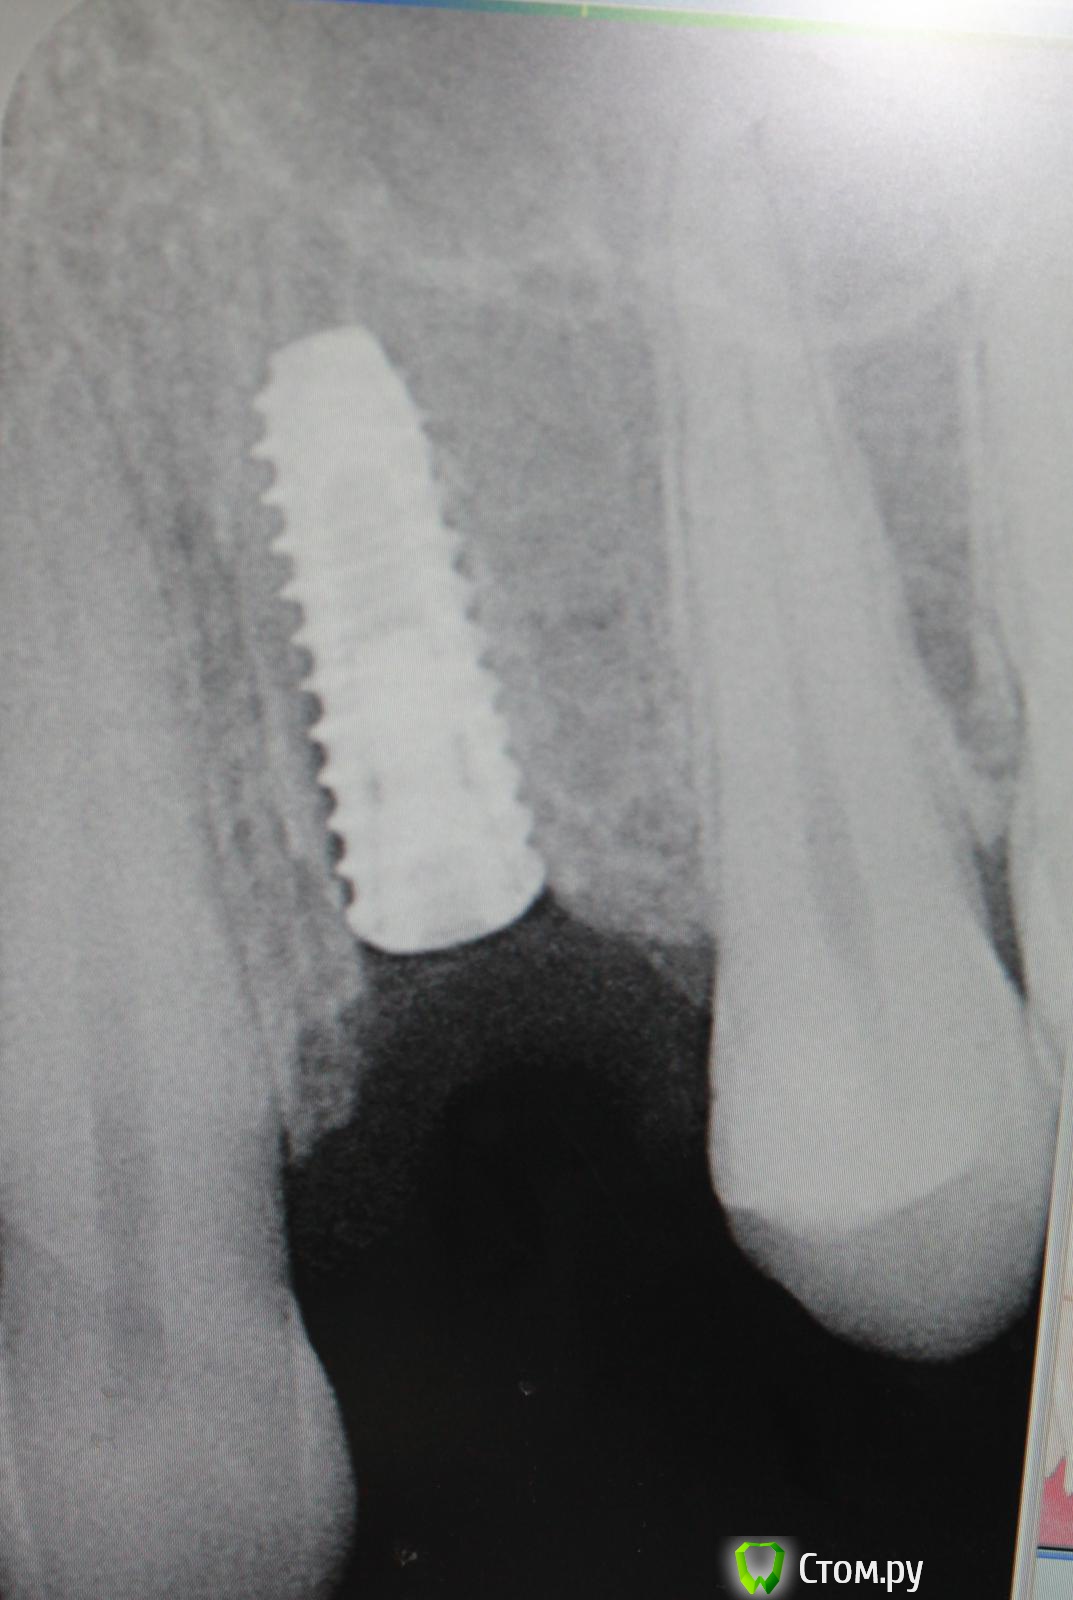

Andex Опубликовано 16 ноября, 2013 Автор Поделиться Опубликовано 16 ноября, 2013 Собственно, возвращаясь к данному кейсу - тоже посчитал, что кисты нет на 25. Удалил 24 и одномоментно проимплантировался. Фото только после операции Ссылка на комментарий

Andex Опубликовано 17 октября, 2013 Поделиться Опубликовано 17 октября, 2013 Всем доброго времени суток. На прием пришла пациентка с желанием удалить 24 зуб и одномоментно проимплантироваться. Стал проводить обследование-а тут сомнения.На панораме 25 явно с кистой(возможно даже в пазуху прорасла)сделал 3D - а там ее нет: Теперь вопросы - кто что думает? Есть она там или нет? Зуб кстати не беспокоил никогда.И каковы мои риски если не удаляя 25 - просто заняться с 24(удаление+имплант). Благодарю за мнения) Ссылка на комментарий

Bier Опубликовано 18 октября, 2013 Поделиться Опубликовано 18 октября, 2013 ну кисты там никакой нет. Даже на орто прослеживается периодонтальная щель. Участок просветления на орто, вызвавший подозрения, скорее всего наложение бухты гайморовой пазухи. 5 Ссылка на комментарий